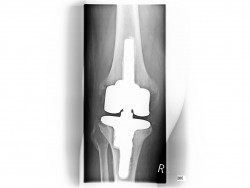

Oberflächenersatz („Knie-TEP“)

Bei einem Verschleiß der gesamten Knorpelfläche bei noch intakten Seitenbändern empfehlen wir einen Oberflächenersatz.

Hierbei werden nur wenigen Millimeter vom Knorpel entfernt um das Implantat passgenau aufzubringen.